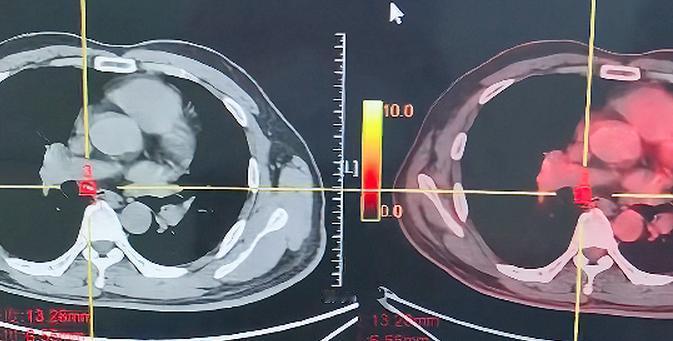

“积德无需人见,行善自有天知”!刚刚完成一台手术,心里挺开心的!患者是一位52岁的男性。 三个月前,我的一位70多岁的老朋友——一位退休干部——带他来找我看病,说他吐血,检查发现肺里有肿块,肿块很大,淋巴结也明显肿大。 老朋友告诉我:患者人特别好,是我们小区的清洁工,恳切地请求我一定要帮帮他,这也让我很感动。 给他做了活检,确诊后进行了三次化疗联合免疫治疗,原本肺部的病灶大约3公分,经过三次治疗后几乎看不见了。 我刚为他做了右下叶切除加淋巴结清扫,手术很顺利,只用了半个小时,手术切下来的部分大约只剩一公分,明显缩小,更关键的是淋巴结的变化:一开始隆突下淋巴结有核桃那么大,从肺门一直蔓延到隆突下;治疗后复查发现已明显缩小。 昨晚老爷子还打电话问我手术危不危险,反复叮嘱一定要保证安全、用最好的治疗。 我很感动,一个普通人能受到大家这样的认可,一定是因为他平时工作认真、待人善良,所以我也特别想帮他。 经过三次化疗联合免疫治疗,肿瘤明显缩小,淋巴结退缩,手术也做得特别顺利。我认为这位患者预后很好,甚至有治愈的可能——他从局部晚期发展到今天这个结果,真的很不容易。 这也让我更加相信,做好人、行好事,或许真的会有好的回报。[作揖][玫瑰]